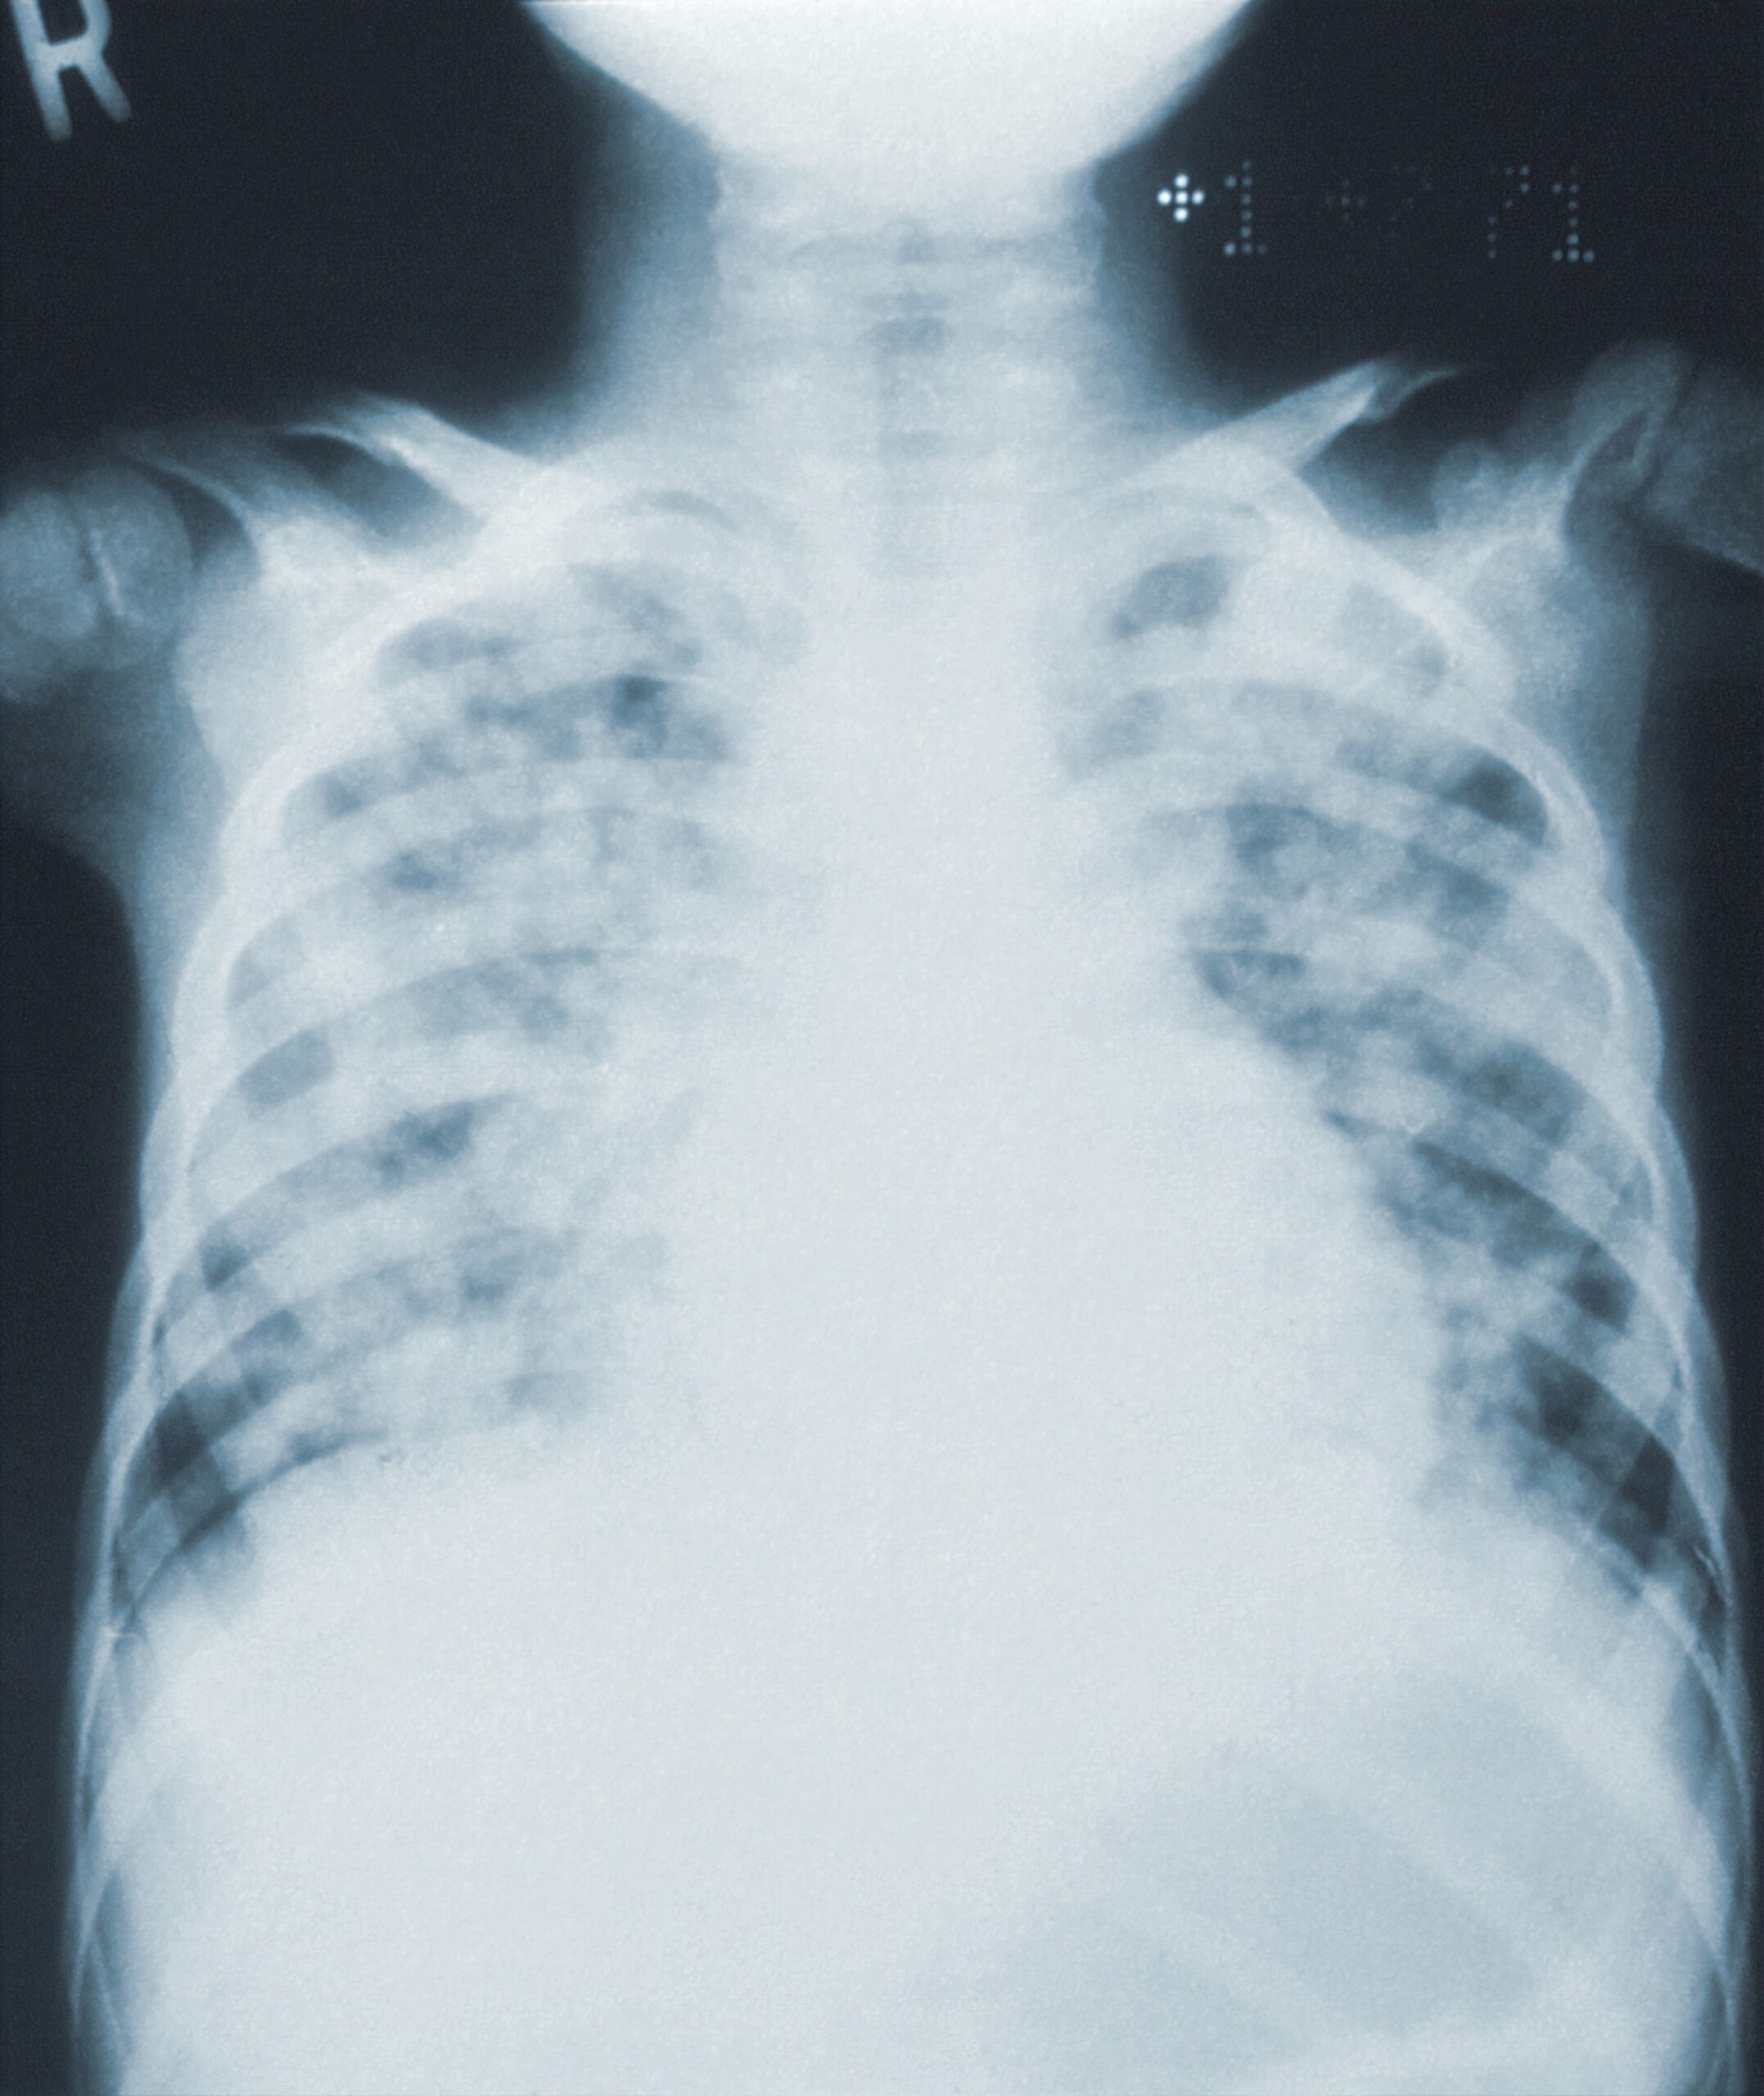

Inclusion: Adult ED patients with a Dx of CAP. CAP defined is as an acute pulmonary parenchymal infection (new infection), usually bacterial that are treatable with anitbiotics (Abx). Causes may be community-, hospital- or ventilator-acquired.

This policy updates evidence/recommendations on current management of ED CAP. CAP is the 8th leading cause of death in the USA, and most common reason for hospital admission (1.5 admissions/year, cost $USD 11,000-51,000 per admit). In Canada, CAP remains one of the most common cause of infection death (Statscan), and is the leading cause of infection death in lower/middle-income countries (LMICs; Michaud 2009). Worldwide, WHO 2020 concluded that lower respiratory tract infections were the #4 cause of death, after CV disease, stroke and COPD. Due to the sheer volume of CAP illnesses, morbidity and mortality, it behooves ED physicians to have an evidence-based approach to risk-stratifying patients who need testing, admission and treatment to avoid excessive illness/deaths, and to yet be prudent resource stewards to optimize high-value care.